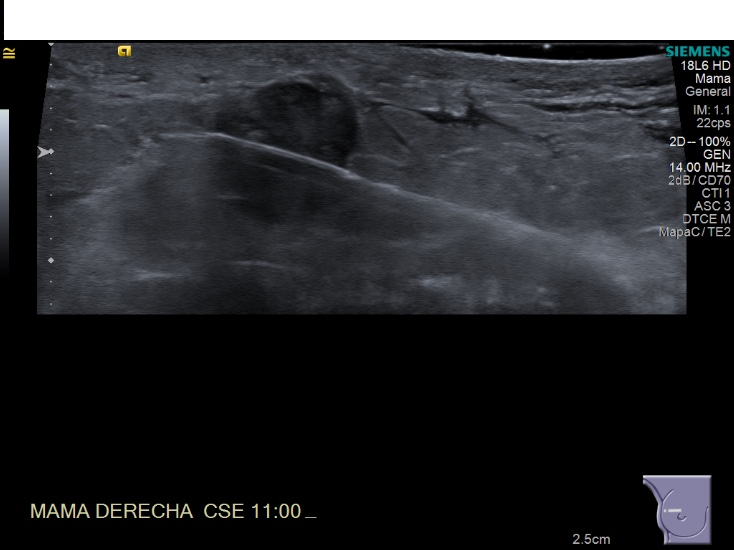

Crioablacion de tumor en mama derecha